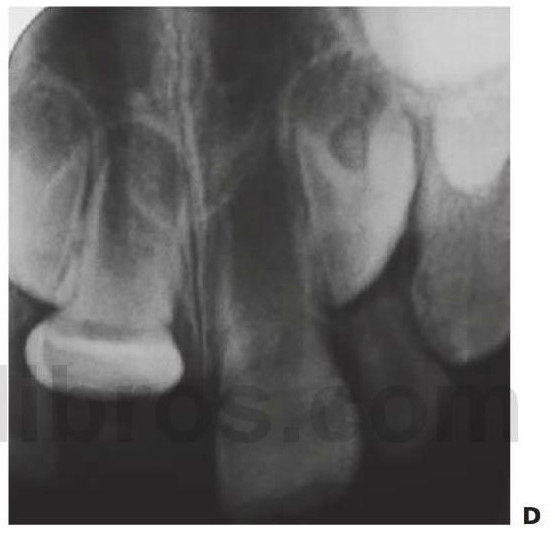

En el caso de las radiografías periapicales, deberán tomarse varias proyecciones de cada uno de los dientes traumatizados para determinar con exactitud la presencia de fracturas de raíz y luxaciones dentales. Como base, deben obtenerse radiografías de todos los dientes que han sufrido un traumatismo a fin de evaluar:

- Estado del desarrollo de la raíz.

- Lesiones en la raíz y en las estructuras de soporte.

Debido a que el cuello del cóndilo es relativamente más ancho en los niños y tiene un volumen mayor de hueso esponjoso, las fracturas de la superficie articular son más habituales que en los adultos. En los casos de fractura intracapsular (figs. 7.5, 7.9), el seguimiento durante años permite detectar cualquier alteración de su crecimiento, y en los casos en que aparezca una limitación de la apertura o una anquilosis franca, se recomienda una intervención temprana con un injerto costocondral.